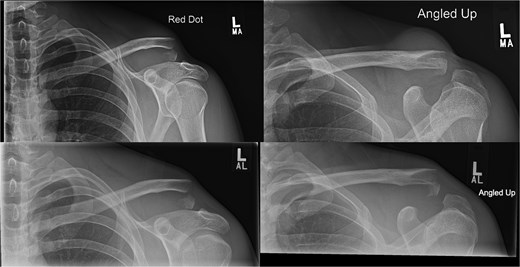

A 15-year-old male sustained a displaced Neer type IV lateral clavicle fracture during a rugby match, presenting with acute pain, deformity, and dorsal displacement without neurovascular compromise (Fig. 1). Imaging confirmed the diagnosis, and open reduction with TightRope and Fiber-wire reinforcement was performed. Early rehabilitation was initiated following short-term immobilization. At 6 weeks, the patient achieved pain-free shoulder function and radiographic stability. By four months, he regained full range of motion and returned to non-contact sports. Minor peri-scar numbness persisted, but imaging confirmed fracture union, and he was cleared for contact activities (Fig. 2A–B).

(A, B) Radiographs showing complete healing of the first case and union at 3 months and 12 months post-operatively.